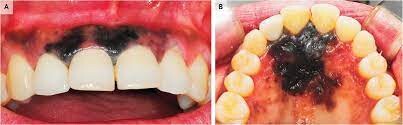

What Causes a Black Spot on Your Gums?

First, we recommend taking a moment to breathe and relax. According to the Oral Cancer Foundation, dark spots rarely indicate a serious condition like cancer and are usually benign. Spots in the mouth are often not fully black but may appear that way as they can be hard to see. We’re here to help walk you through the causes of dark spots in your mouth and what they mean.

Causes of Dark Spots on Gums

Oral conditions like dark spots on your gums have various causes and can be challenging to diagnose. These spots can either be harmless or the result of an underlying disease, so it's essential to speak to your doctor if you believe you have any symptoms.

What exactly causes black spots on your gums? There are two categories of answers: those with internal causes and those with external causes.

Did you know: Internal causes are called endogenous and external causes are called exogenous.

Internal Causes

Internal pigments that cause skin colour changes can also modify your gums' colour to black, grey, blue, or brown. Blood vessels can even dysfunction or rupture, leading to discolouration.

Melanin can be altered by a variety of diseases and disorders that affect the production of this pigment. Cells in your body that produce melanin are called melanocytes.

Tuberculosis and Addison's disease can affect your adrenal glands and cause changes in pigmentation.

HIV, also called the human immunodeficiency virus, can lead to pigmented lesions in the mouth.

According to a research article published in the Journal of Indian Academy of Oral Medicine and Radiology, haemangiomas are most common soft tissue benign tumours, composed of blood vessels, and occur in the head and neck region (60%) and less commonly in the oral cavity; oral cavity if affected involves gingiva followed by the lips, tongue and palate.

External Causes

Exposure of your mouth to pigment produced outside the body can lead to discolouration in the form of dark or spots on the gums. Sources outside the body can also affect your body's production or regulation of pigment or iron, leading to a change in colour. These black dots can be caused by:

Drugs (prescription, over-the-counter and illegal)

Smoking and tobacco products

Trauma to the face or mouth

Heavy metals

Injury from graphite pencil

An old filling (also known as a dental amalgam)pushing into the gums

Oral Cancer

In rare cases, benign lesions that don't require treatment may transform into oral malignant melanoma, a type of oral cancer. A doctor will look at a range of factors to see if the lesion qualifies as melanoma. According to a research article published in the Journal of Indian Academy of Oral Medicine and Radiology, melanoma constitutes only 3–5% of all cutaneous malignancies, and oral melanoma is an aggressive neoplasm which accounts for less than 0.5%.

If you believe you have oral cancer symptoms, we recommend leaving the diagnosis up to the professionals and speaking to your doctor. If you exhibit symptoms, they may perform a biopsy (laboratory tests of your tissue) to confirm melanoma.

Remember that cancer is a rare cause of any dark spots in your mouth. A more benign explanation is much more likely, so don't stress. You've done a great job informing yourself of the possible causes, so be sure to make the next step for success and schedule an appointment or regular check-ups with your doctor.